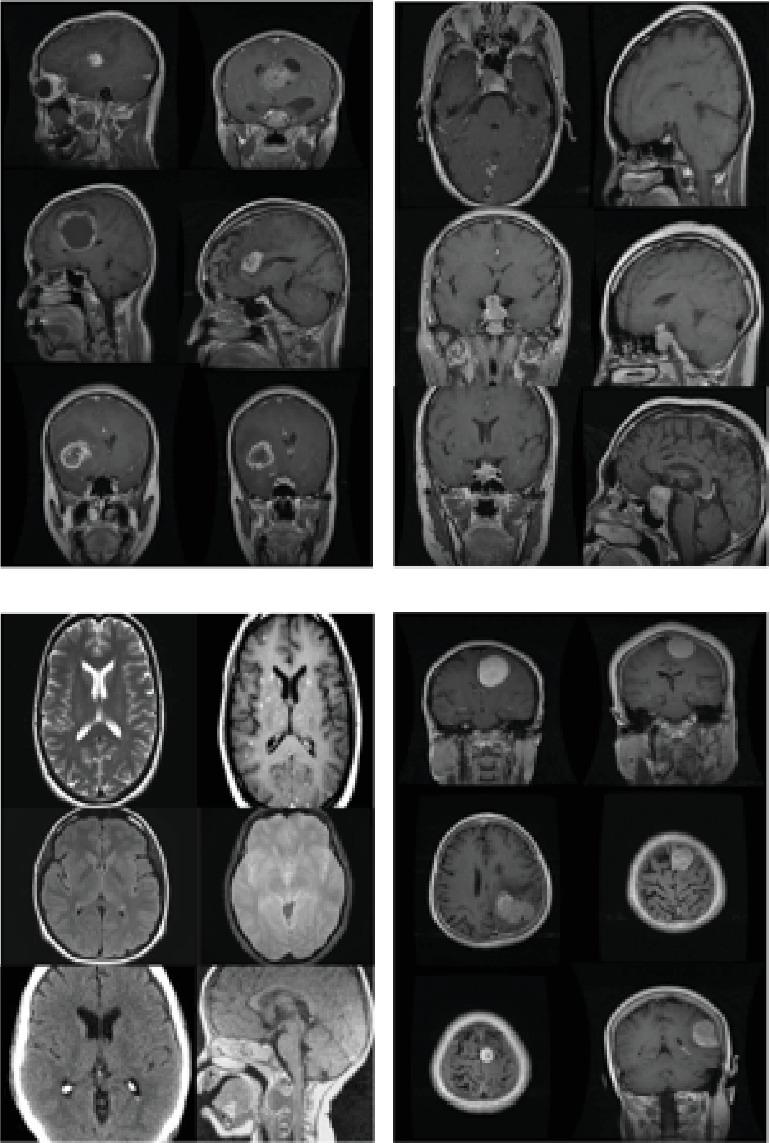

The objective of AI research and development is to create intelligent systems capable of performing tasks and reasoning like humans. Artificial intelligence extends beyond pattern recognition, planning, and problem-solving, particularly in the realm of machine learning, where deep learning frameworks play a pivotal role. This study focuses on enhancing brain tumour detection in MRI scans using deep learning techniques. Malignant brain tumours result from abnormal cell growth, leading to severe neurological complications and high mortality rates. Early diagnosis is essential for effective treatment, and our research aims to improve detection accuracy through advanced AI methodologies. We propose a modified DarkNet-53 architecture, optimized with invasive weed optimization (IWO), to extract critical features from preprocessed MRI images. The model's presentation is assessed using accuracy, recall, loss, and AUC, achieving a 95% success rate on a dataset of 3264 MRI scans. The results demonstrate that our approach surpasses existing methods in accurately identifying a wide range of brain tumours at an early stage, contributing to improved diagnostic precision and patient outcomes.

Abstract Image